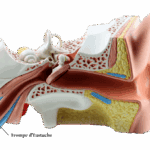

Rééducation tubaire

De l’oreille au mieux-être des patients : formez-vous à la rééducation tubaire